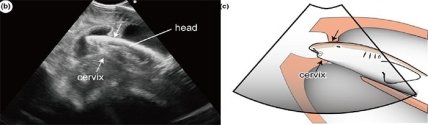

Данные ученых показали частую миграцию эмбрионов между правой и левой матками, это открытие было сделано благодаря новому ультразвуковому оборудованию, предназначенному для сканирования человеческой беременности. Портативные сканеры использовались в течение нескольких лет, даже чтобы заглянуть внутрь акул, однако это было затруднено тем, что рыба извлекалась из привычной среды обитания.

Чтобы изучить их в более естественном состоянии, ученые усовершенствовали свое устройство, сделав его устойчивым к воздействию влаги и давления. Несколько лет исследователи изучали трех беременных акул, сделав более 40 ультразвуковых клипов, на которых можно было увидеть до четырех акулят, извивающихся внутри каждой матери.

У одной матери эмбрионы трижды поменялись местами. В другом случае движение было гораздо более интенсивным: всего было зарегистрировано 24 миграции в течение всей беременности. На одном из снимков было показано, как произошел фактический обмен матками, а один из зародышей поспешно продвигался от одной матки к другой. Его скорость составляла восемь сантиметров в секунду, что поразило ученых. Еще одна акула на ранней стадии беременности имела по два эмбриона в каждой матке. Спустя некоторое время их стало на одним меньше. Через еще два месяца осталось лишь два зародыша, а к концу беременности — только один победитель.